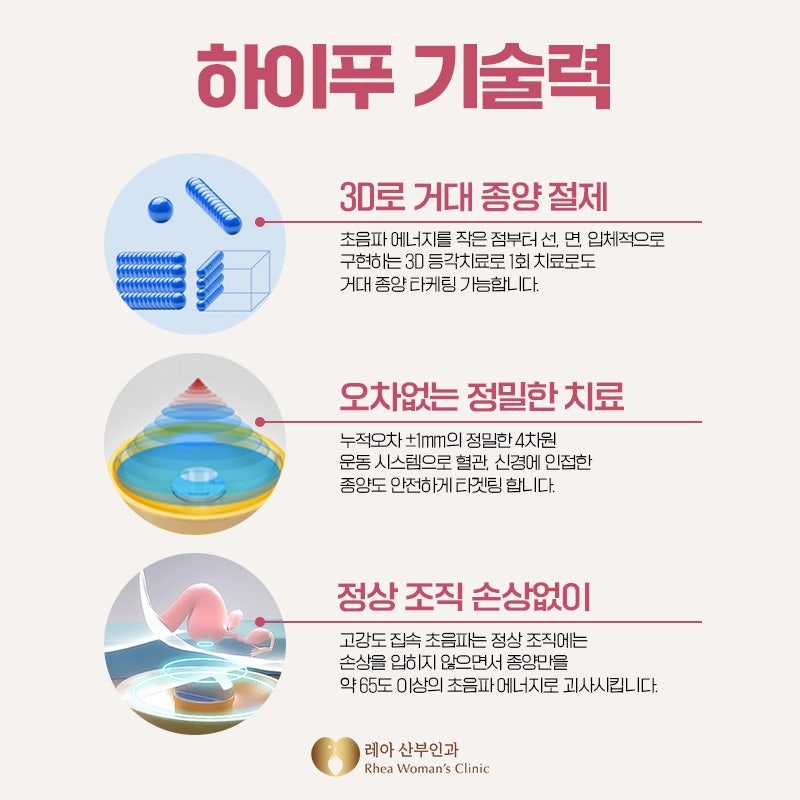

자궁에 발생하는 질환 중 대표적으로 알려진 것은 자궁근종과 자궁선근증, 다낭포성난소증후군 등인데 젊은 임신기 여성은 물론 중년 여성까지 연령에 상관없이 발생하고 있으며 그 중에서도 35세 이상 여성에게서 40~45% 정도가 겪고 있을 정도로 흔한 질환이 자궁근종이었습니다.발생한 위치에 따라 증상이 다르지만 경우에 따라서는 통증과 부정출혈을 동반할 수 있어 불임, 난임, 유산에 영향을 미치므로 임신 중인 여성이라면 반드시 정기적으로 자궁검진을 실시하여 예방과 적절한 치료가 이루어지도록 하는 것이 중요했습니다.자궁근종 하이프 시술은 자궁질환을 치료하는 가장 효율적인 방법으로 알려져 있으며 자궁선근증에도 활용되고 있었습니다.발생 위치에 따른 구분자궁근종은 자궁근육층에 근종이 발생한 것으로, 1cm 미만 크기부터 12cm 이상의 거대 근종까지 다양하게 확인됐습니다.개수나 위치에 따라 증상이 다르고 적절한 치료시기와 방법이 다르기 때문에 진단을 받는 과정에서 의료진의 숙련도와 임상경험 유무 및 검사장비와 치료장비 등 의료적 환경이 적절하게 갖춰져 있는지 확인하는 것이 중요했습니다.근층내근종가장 흔하게 발생하는 자궁근종으로 근육 중간 부위에 근종이 발생하여 자궁을 비대화시키고 내막을 확장시켜 복부압박감과 부정출혈 및 평소보다 많은 생리를 유발하였습니다. 장막하근종자궁 바깥쪽에 위치한 장막층에서 발생한 것으로 근종이 커지고 하복부에 대한 불쾌감이 심해져 근층 내 근종 다음으로 많이 발생했습니다.하복부가 볼록하게 돌출되어 빈뇨감과 잔뇨감을 느끼거나 배뇨 및 배변 장애를 겪는 경우가 자주 있었습니다. 점막하근종자궁 내 점막에서 발생하는 근종으로 크기에 관계없이 출혈이나 심한 생리통을 유발하고 임신에도 영향을 미치게 되었습니다.잦은 출혈로 빈혈을 일으키고 자궁 내부에 위치하기 때문에 불임은 물론 유산이나 조산에 결정적인 요인이 되는 경우가 많아 즉시 치료가 필요했습니다.자궁근종이 의심되는 증상발생 위치와 개수 및 크기에 따라 치료 여부가 달라졌고 자궁 건강에 미치는 영향도 모두 달랐습니다.하지만 자신의 몸에 있어서는 안 되는 비정상적인 조직인 것만은 변하지 않기 때문에 의심 증상을 알아두고 체크해서 조기 치료를 할 수 있도록 하는 것이 무엇보다 중요했습니다.생리통이 항상 심하게 느껴졌어요.생리 전 하복부 통증과 골반 안쪽 통증이 심했습니다.생리 중에 출혈량이 많았어요.생리 중 빈혈 증상을 경험했어요.부정출혈을 자주 경험했어요.아랫배가 중후해서 통증과 압박감을 잘 느꼈어요.아랫배가 나와서 가스가 잘 찼어요.잔뇨감과 빈뇨감으로 불편함을 느꼈습니다.아랫배와 복부에 단단한 막대기가 닿았어요.자궁근종 치료법근종의 종류나 임신력 등을 고려해서 치료 방법을 선택하는데 수술적인 치료인 복강경과 비수술적인 치료인 자궁내시경과 자궁근종 용해술 그리고 하프 시술이 있었습니다. 이 중 자궁근종 하이프 시술은 체력적 부담을 줄임과 동시에 자궁을 보존할 수 있는 방법으로 대중적인 인기를 얻고 있으며 자궁 손상을 피하고 자궁이나 임신력을 보존하는 데 최적화된 방법이라고 할 수 있습니다.하이푸는 고강도 집속 초음파 장비는 JC200D를 사용하는데, 다만 자궁근종과 자궁선근증 치료를 목적으로 개발된 장비였습니다. 고강도 집속 초음파가 복부를 투과해 근종만을 찾아 고온에서 괴사를 유도함으로써 실시간 모니터링과 1.1mm 미세초점으로 움직이면서 타겟팅할 수 있어 근종의 위치와 크기에 관계없이 정확하게 치료할 수 있었습니다.비용이 아닌 결과가 중요한 치료여성에게 자주 발생하는 자궁근종이지만 제대로 치료하지 않으면 재발이 잦아 임신이나 출산에 악영향을 미칠 수 있었습니다. 따라서 비용적인 부분을 보기 전에 다양한 임상 경험을 가진 의료진이 진료를 책임지고 있는지 자궁을 살릴 수 있는 하이프를 우선시하는지 먼저 알아보는 것이 좋았습니다.레아산부인과에서는 병변 위치를 명확히 확인할 수 있도록 시술 전후 2회에 걸쳐 MRI 촬영을 실시하였으며, 산부인과 전문의이자 가톨릭대학교 외래교수인 이경숙 원장이 직접 진료하고 있는 만큼 1:1 맞춤 치료로 건강한 생활과 건강한 신체를 유지하기 위해 필요한 지원을 받을 수 있었습니다.여성에게 자주 발생하는 자궁근종이지만 제대로 치료하지 않으면 재발이 잦아 임신이나 출산에 악영향을 미칠 수 있었습니다. 따라서 비용적인 부분을 보기 전에 다양한 임상 경험을 가진 의료진이 진료를 책임지고 있는지 자궁을 살릴 수 있는 하이프를 우선시하는지 먼저 알아보는 것이 좋았습니다.레아산부인과에서는 병변 위치를 명확히 확인할 수 있도록 시술 전후 2회에 걸쳐 MRI 촬영을 실시하였으며, 산부인과 전문의이자 가톨릭대학교 외래교수인 이경숙 원장이 직접 진료하고 있는 만큼 1:1 맞춤 치료로 건강한 생활과 건강한 신체를 유지하기 위해 필요한 지원을 받을 수 있었습니다.희아산부인과의원 서울특별시 강남구 강남대로 340 4층희아산부인과의원 서울특별시 강남구 강남대로 340 4층희아산부인과의원 서울특별시 강남구 강남대로 340 4층희아산부인과의원 서울특별시 강남구 강남대로 340 4층희아산부인과의원 서울특별시 강남구 강남대로 340 4층희아산부인과의원 서울특별시 강남구 강남대로 340 4층